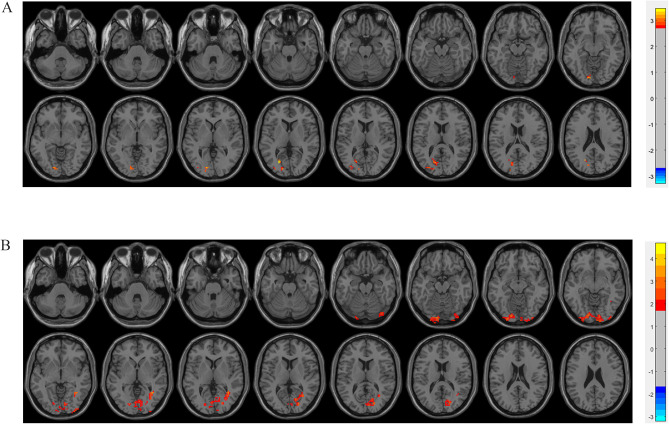

Patients and methods: Patients (aged ≥65 years) were randomized into Groups C (n=88) and E (n=93). Patients in Group E received multimodal brain monitoring-guided anesthesia management, and those in Group C received BIS-guided anesthesia management. The Montreal Cognitive Assessment (MoCA) was performed both before and seven days after surgery. The postoperative pain scores were recorded. Resting-state functional MRI data were analyzed to examine functional connectivity (FC).

Results: Group E demonstrated a numerically lower incidence of PND (15.50% vs 21.59% in Group C), but this difference was not statistically significant. Patients in Group E had increased FC within the right pulvinar, right sub-gyral region, and right inferior parietal lobule (P < 0.05). Significantly lower pain scores were observed in Group E at rest (1h: P=0.04; 24h: P=0.04) and during movement (1h: P=0.03).

Conclusion: These results suggest that multimodal brain monitoring-guided anesthesia management may protect neurocognition by enhancing FC within cognition-associated brain regions and attenuating postoperative acute pain. And multimodal brain monitoring-guided anesthesia management may confer a clinically relevant reduction in PND incidence compared to BIS-guided management in elderly surgical patients.